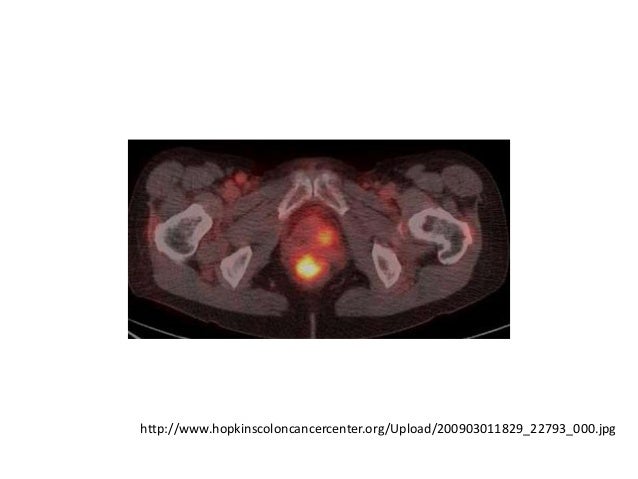

60. 60. http://www.hopkinscoloncancercenter.org/Upload/200903011829_22793_000.jpg

86. 86. 61歳男性• 経口CY + PSLで治療開始 – 当初IVCYだったがコントロールつかず、経口に切り替え• その後、関節症状・血管炎症状とも寛解• 40℃の発熱(quotidian fever)・汎血球減少症で入院• WBC 3000, Hb 5.5, Plt 80K• 骨髄生検: ↑MgK、↑MΦ• 画像検査: 熱源の同定に至らず• 英国NHS → FDG-PET uncovered Rheumatology 2006; 45: 386-91